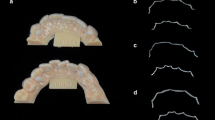

Relevant information, such as alloy components of the retainer materials and production methods, were obtained prior to the study from the respective manufacturer (Table 1). For the design of the CAD/CAM retainers, maxillary and mandibular alginate impressions were taken from a male volunteer (aged 35) to produce plaster models from super-hard dental stone (Hinrizit, Ernst Heinrichs GmbH; Goslar, Germany). The models were then digitized by use of a desktop scanner (Ortho X, Dentaurum; Ispringen, Germany) and the derived STL data were used to order the CAD/CAM retainers from the respective manufacturer (Fig. 1). The Twistflex retainers were bent on conventional plaster models.